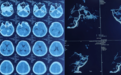

到达神经外三科后,科主任王玉亭组织疑难病例讨论,制定治疗计划,行脑血管造影(DSA)检查,诊断为颅内巨大动静脉漏合并蛛网膜下腔出血。蛛网膜下腔出血是妊娠期少见且严重的并发症,孕妇及胎儿的死亡率较高,以动脉瘤最多见,而脑动静脉瘘极少见。考虑患者刚刚分娩,较为虚弱,决定行脑动静脉瘘微创介入栓塞术。